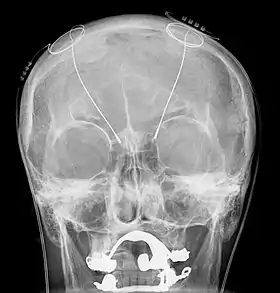

The DBS system consists of three components: the implanted pulse generator (IPG), the lead, and an extension. The IPG is a battery-powered neurostimulator encased in a titanium housing, which sends electrical pulses to the brain that interfere with neural activity at the target site. The lead is a coiled wire insulated in polyurethane with four platinum-iridium electrodes and is placed in one or two different nuclei of the brain. The lead is connected to the IPG by an extension, an insulated wire that runs below the skin, from the head, down the side of the neck, behind the ear, to the IPG, which is placed subcutaneously below the clavicle, or in some cases, the abdomen.[9] The IPG can be calibrated by a neurologist, nurse, or trained technician to optimize symptom suppression and control side effects.[36]

All three components are surgically implanted inside the body. Lead implantation may take place under local anesthesia or under general anesthesia ("asleep DBS"), such as for dystonia. A hole about 14 mm in diameter is drilled in the skull and the probe electrode is inserted stereotactically, using either frame-based or frameless stereotaxis.[38] During the awake procedure with local anesthesia, feedback from the person is used to determine the optimal placement of the permanent electrode. During the asleep procedure, intraoperative MRI guidance is used for direct visualization of brain tissue and device.[39] The installation of the IPG and extension leads occurs under general anesthesia.[40] The right side of the brain is stimulated to address symptoms on the left side of the body and vice versa.